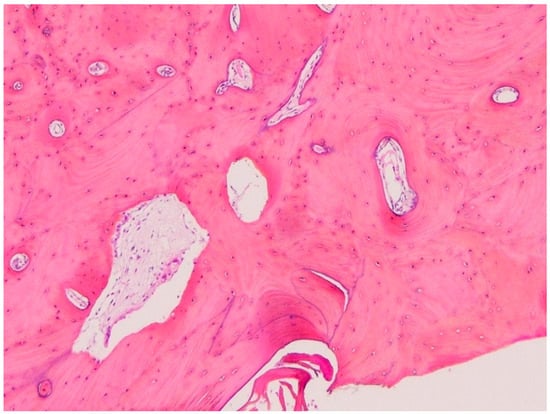

2. Case Presentation